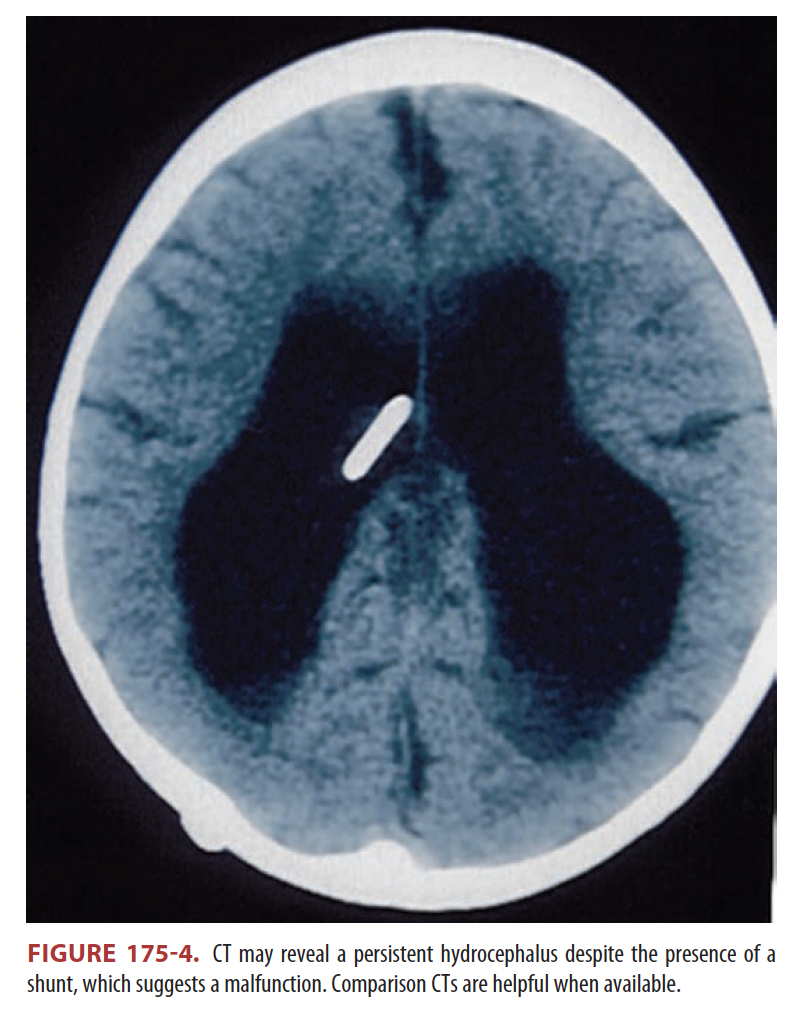

Remarks on CT scan results in patients with suspected shunt malfunction

**Compare with previous CT scans because many patients with shunts have an abnormal baseline ventricular size.** **Unremarkable findings on CT and/or radiographic shunt series cannot be relied on to exclude shunt obstruction**ª **Thus, obtain neurosurgical consultation whenever shunt malfunction is suspected** ## Footnote ª*Between 9% and 15% of pediatric patients will have profound alterations in brain compliance leaving ventricular size unchanged even in profound shunt failure with high intracranial pressures.*